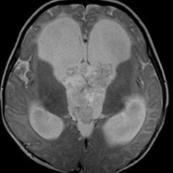

• 脈絡叢乳頭狀瘤

628健康網為您分享有關脈絡叢乳頭狀瘤的癥狀,脈絡叢乳頭狀瘤的治療方法,脈絡叢乳頭狀瘤的預防知識,脈絡叢乳頭狀瘤的癥狀...